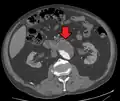

An axial contrast-enhanced CT scan demonstrating an abdominal aortic aneurysm of 4.8 by 3.8 cm -